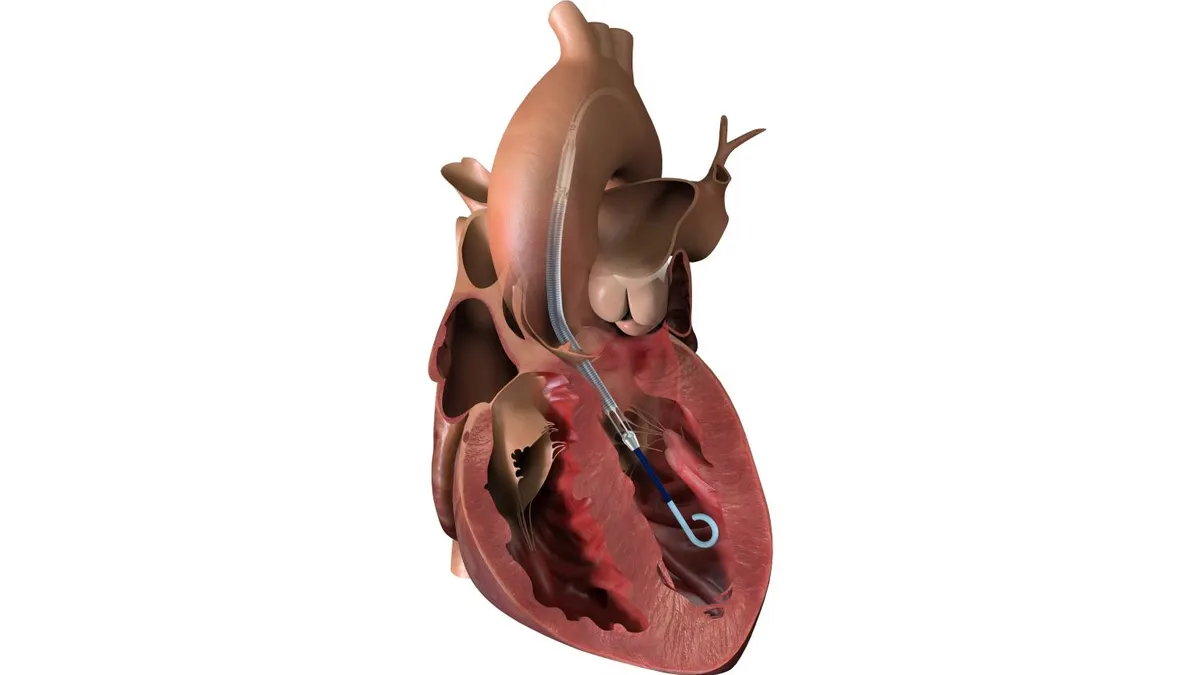

CMS is also expected to release some key national coverage determinations in the coming weeks. They include a final NCD on next generation sequencing that will lift restrictions on the tests for patients whose genetics may put them at risk for developing cancer and those with earlier-stage cancers. Also coming down the pike is a draft NCD on transcatheter mitral valve repair, expected to be finalized in May.